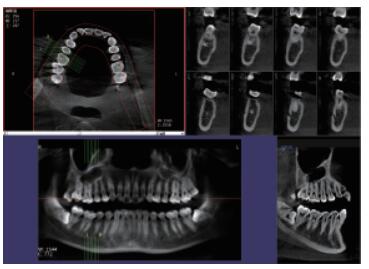

4、口腔CBCT(口腔CT)

CT相對其他牙片來講,不管是功能還是設(shè)備上都是比較高級的,醫(yī)生可在電腦上進(jìn)行模擬種植360°的旋轉(zhuǎn)查看口腔狀況,不遺漏任何一個角落,主要用于根管治療前、阻生牙、根尖囊腫、種植牙、正畸等。